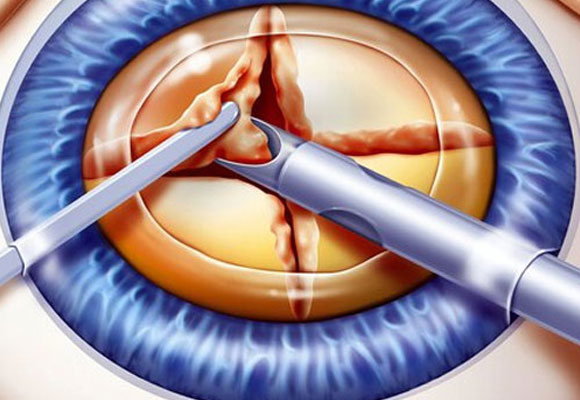

Dr. Abdul Rasheed, one of the leading Ophthalmologist and Cataract & Refractive surgeon in the city of Hyderabad provides extensive and comprehensive care for all your eye sight issues. Vision disturbance are one of the few issues which have the capacity to completely disturb our daily life and activities. Correcting them in the right way to avoid further complications or risk is the motto of Dr. Abdul Rasheed. With age comes cataract, Dr.Rasheed is an expert in complicated cataracts such as small pupil, zonular dialysis, mature / Brunescent cataracts, corneal scars, shallow Ac, etc., as well as complicated refractive surgery cases like RK scars, corneal scars, etc. While coming to refractive surgeries, Dr. Abdul Rasheed strongly believes and says "Any patient irrespective of complexity, who can be refracted to 6/6 can be treated to read the same without glasses." He has treated many patients of keratoconus who had extreme distortion of vision. After INTACS implantation followed by ICL, patients were able to regain normal vision.